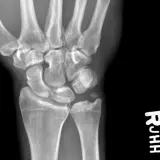

Casos totalmente interactivos con las herramientas que esperaría de un PACS: scroll, ventana, zoom, pan, mediciones, ROI y modo de pantalla completa.

• Anotaciones enlazadas

Anotaciones extensas resaltan los hallazgos clave directamente sobre los casos. Haga clic en los hallazgos enlazados dentro de la descripción del caso para saltar a su ubicación exacta en el estudio.